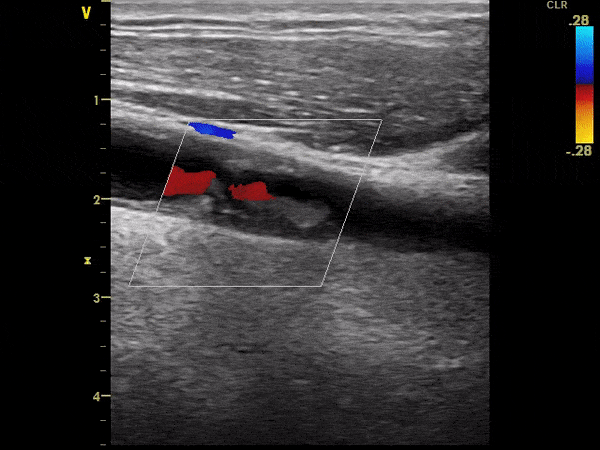

Ekografi e vazave të qafës

Ekografi e arterieve karotide dhe e arterieve vertebrale triplex (2D, color, doppler). Me anë të këtij ekzaminimi:

• Shihet pllaka arteriosklerotike.

• Përcaktohet përqindja e ngushtimit të arteries karotide.

• Përcaktohet forma, gjatësia dhe vendndodhja e saktë.

• Përcaktohet lloji i pllakës arteriosklerotike. Nëse është e butë, e çrregullt, jo e kufizuar mirë nga kapsula e saj – ajo mund të çahet dhe të shkaktojë insult cerebral trombotik.

Pamje të kapura me ekografi të vazave të qafës: